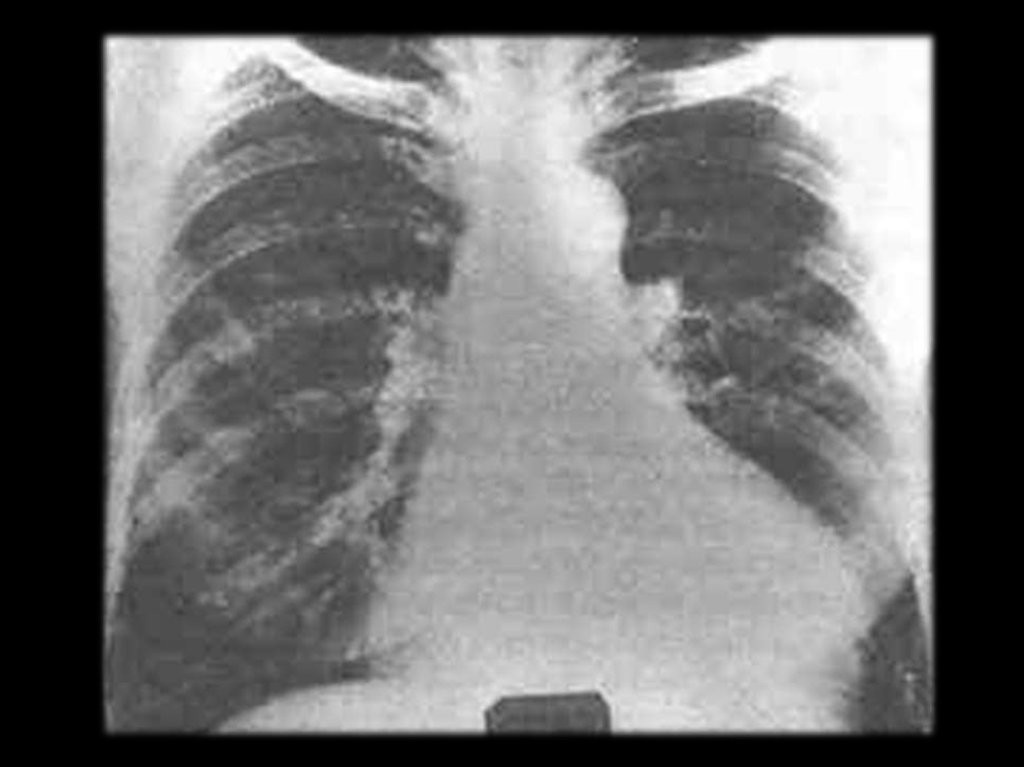

Лёгкие – 30 – 80%.

Прогрессирующий

пневмосклероз,

преимущественно в базальных отделах.

31.

«Сотовое лёгкое»